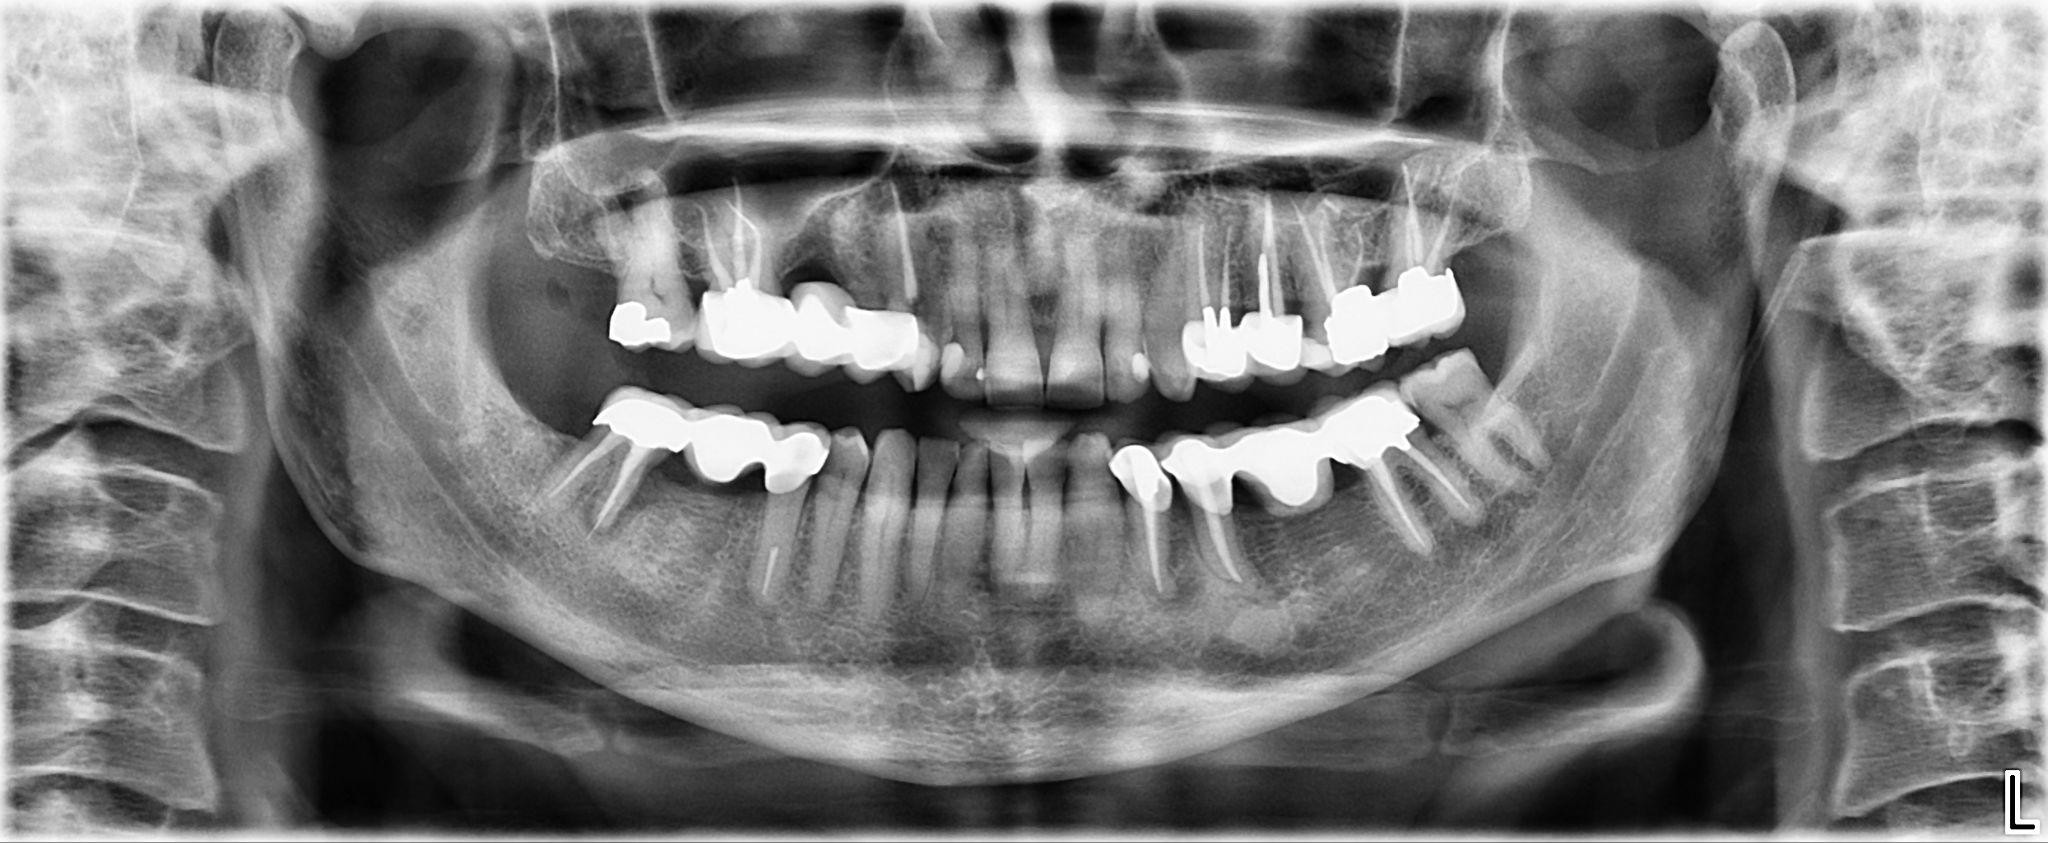

1. What option cannot be selected for the first quadrant of this panoramic X ray?

2 / 25

2. What option cannot be selected for the second quadrant of this panoramic X ray?

3 / 25

3. What option can be selected for the third quadrant of this panoramic X ray?

4 / 25

4. What option cannot be selected for the forth quadrant of this panoramic X ray?